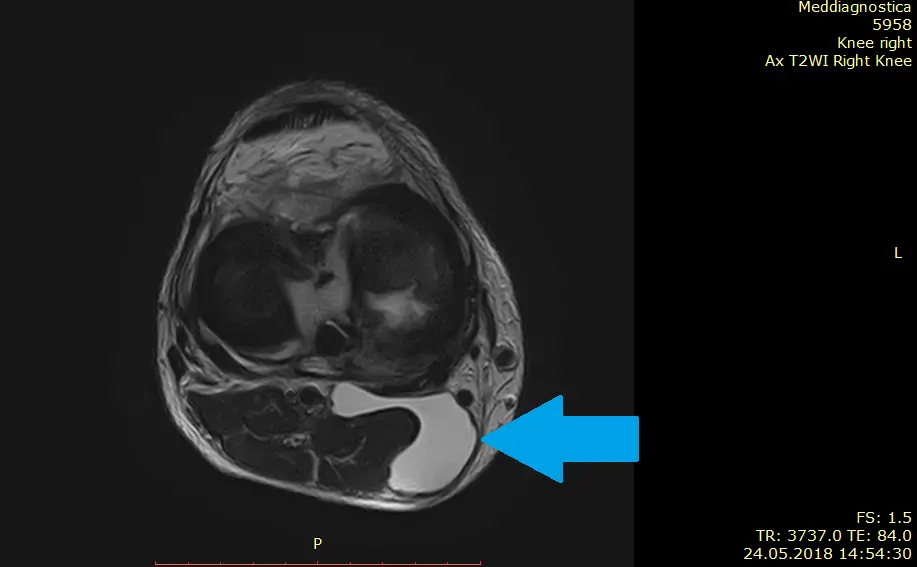

Киста Бейкера на МРТ

Диагностируют кисту Бейкера при помощи клинического осмотра пациента, УЗИ исследования коленного сустава. Киста подколенной ямки хорошо видна на МРТ. Показана рентгенография сустава для обзорной оценки соотношений бедренной и большеберцовой костей, хрящей и мягких околосуставных тканей. Рентген позволяет исключить возможные сопутствующие заболевания (артроз, опухоли сустава, процессы обменного характера и др.). Важным сегментом диагностики являются лабораторные исследования для выявления причины воспаления капсулы сустава.

Киста Бейкера – непростое заболевание. Оно требует выверенных подходов к диагностике и лечению. Для диагностики используют специальное оборудования и соответствующие технологи: УЗИ диагностика, рентген колена, МРТ коленного сустава.